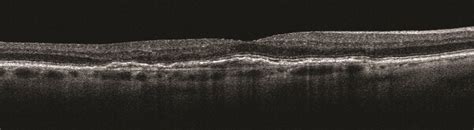

Oct Double Layer Sign

Oct Double Layer Sign. This sign is indicative of an abnormal choroidal. From $150.00 oh baby double layer.